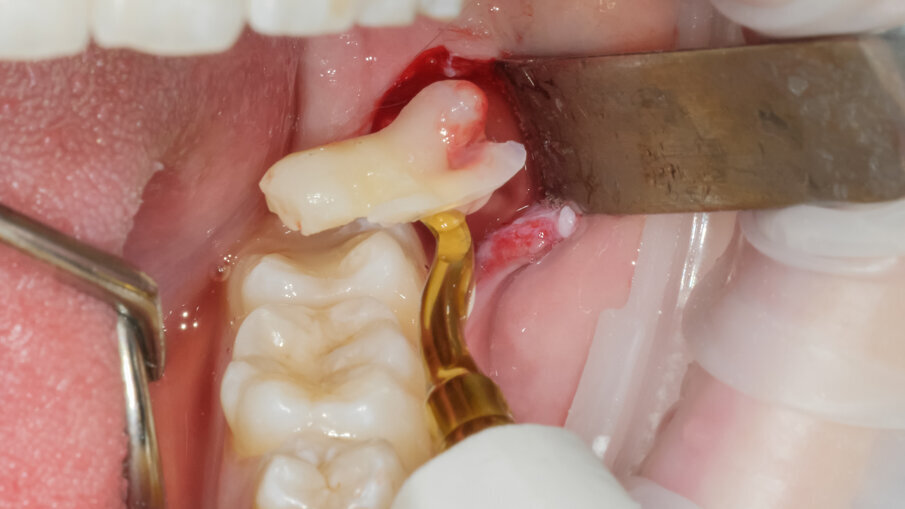

L’ostectomia di accesso per evidenziare la corona è stata praticata mediante inserto SLO-H. Questo inserto nasce per il disegno della botola ossea nel rialzo di seno laterale, ma per la sua forma e il forte potere tagliente risulta molto efficace anche nella ostectomia peridentale (Figg. 3, 4). Mediante fresa a fessura in carburo di tungsteno montata su manipolo diritto sotto costante irrigazione di fisiologica sterile si è proceduto alla fase di odontotomia verticale in modo da separare la porzione corono radicolare mesiale da quella distale (Fig. 5).

La scelta condivisa è quella di utilizzare la tecnologia piezolettrica per le fasi di odontotomia, solo nelle zone di difficile accesso o in prossimità di strutture anatomiche a rischio come il nervo alveolare inferiore. Per la fase di lussazione si è applicato il protocollo descritto da Fontanella utilizzando il nuovo inserto EXL1 (Figg. 6, 7). Questo inserto insieme agli altri due inserti lussativi (EXL2, EXL3) hanno la particolarità di sfruttare l’impulso piezoelettrico associato al movimento lussativo dell’inserto montato sul manipolo. La cavità residua è stata gestita rimuovendo i residui di sacco follicolare e detergendo il sito post estrattivo sfruttando l’effetto cavitazionale della tecnologia piezoelettirca (Fig. 8). Il lembo riposizionato è stato suturato con chiusura per prima intenzione con punti singoli riassorbibili 4/0 (Fig. 9). Al controllo post operatorio la ferita presentava una guarigione nella norma, e la paziente riferiva un post operatorio senza particolare gonfiore e con assunzione di antidolorifico solo nel primo giorno post chirurgico